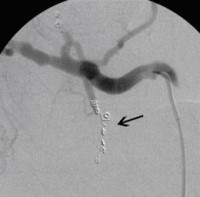

Postoperative abdominelle Blutungen bei chronischer Pankreatitis (Pfeile: Art. hepatica und Art. gastroduodenalis). (Bild 1 von 5) Vorwärts »

« Zurück Postoperative abdominelle Blutungen bei chronischer Pankreatitis vor Embolisation der Art. gastroduodenalis mittels Metallspiralen (Coils) (Bild 2 von 5) Vorwärts »

« Zurück Postoperative abdominelle Blutungen bei chronischer Pankreatitis nach Embolisation der Art. gastroduodenalis mittels Metallspiralen (Coils) (Bild 3 von 5) Vorwärts »